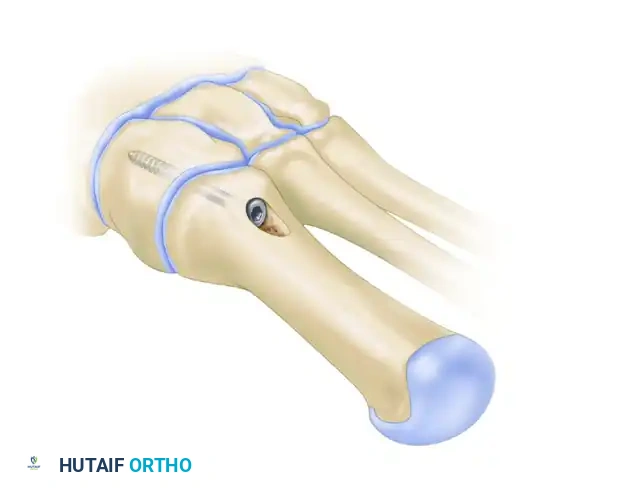

- Pre-drilling the Glide Hole: Crucial Step. Drill a 3.5-mm glide hole at the 2-cm mark (1 cm distal to the planned osteotomy) in the center of the metatarsal shaft, directing it proximally. Performing this before the osteotomy ensures absolute stability during drilling.

- Place a centering device ("golf tee" or "mushroom" guide) into the pre-drilled 3.5-mm glide hole.

- Insert a 4.0-mm fully threaded cancellous screw (typically 26 mm in length).

Clinical Pearl: Countersinking is Mandatory

Use a countersink in the dorsal glide hole before inserting the screw. This gently removes cortical bone from the distal hole, allowing the screw head to sit flush. If omitted, the screw head will abut the dorsal cortex during the final turns, acting as a wedge that will inevitably fracture the intervening cortical bone bridge, leading to catastrophic loss of fixation.